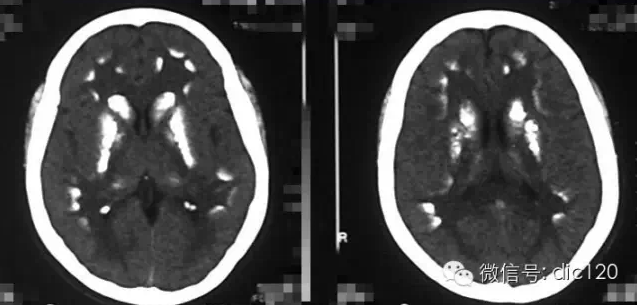

診斷小腦萎縮通常需要進行神經系統檢查、影像學檢查(如腦部CT或MRI)和實驗室測試,治療小腦萎縮的方法主要包括藥物治療、物理治療和康復訓練等,藥物治療旨在緩解癥狀和改善生活質量,物理治療幫助患者恢復肌肉力量和運動功能,康復訓練則包括語言治療、認知訓練和心理支持等。